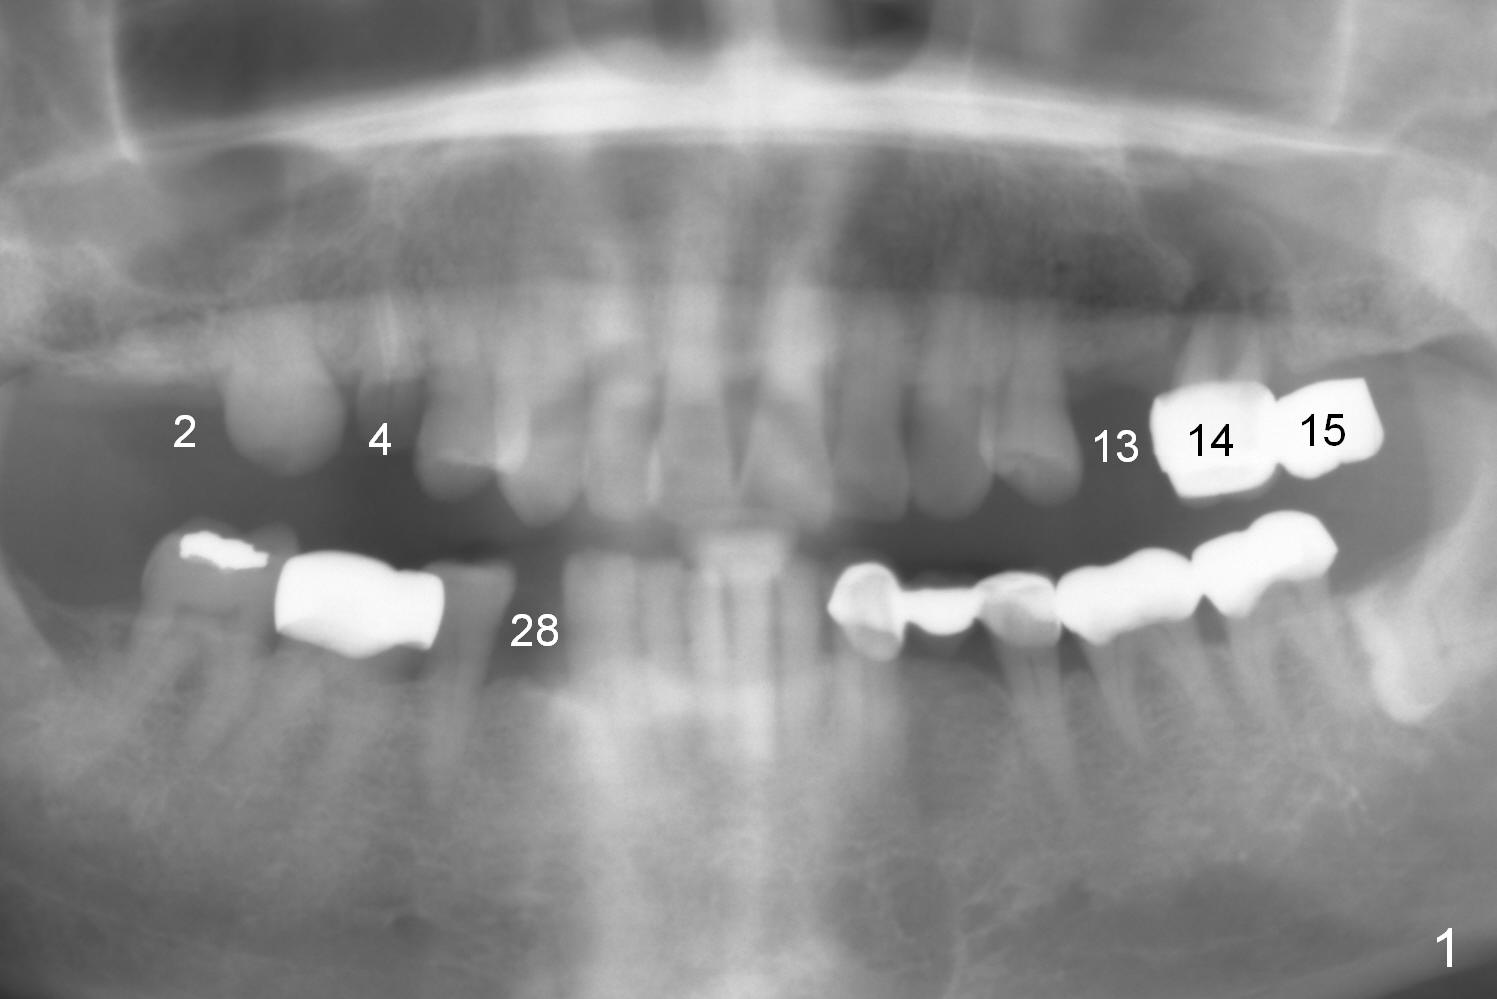

The 72-year-old man will return for #13-15 implantation after that at #2/4 and 28. There is severe wear in the cingula of the upper anterior teeth due to posterior collapse (several missing teeth, residual root and failing restoration, Fig.1). Prior to removal of the cantilever bridge (#14.15), an implant is placed at #13 (Fig.2). If the defect at #14 is too large after extraction, an implant is placed at #15 with an immediate provisional bridge (Fig.3 white line). Otherwise a large implant (possibly Tatum tapered) will be placed at #14 (Clindamycin) with splinted immediate provisional (Fig.4). Allograft is expected for sinus lift at #14 and 15 (Fig.3,4 red circles with Osteogen in 3:1 ratio). For socket preservation at #14, mix equal amount of allograft and Osteogen (Fig.3 pink), followed by Collagen plug (yellow) and the pontic of the provisional bridge. Prepare PRF (3-4 tubes of blood, one of them to be made for a plug).